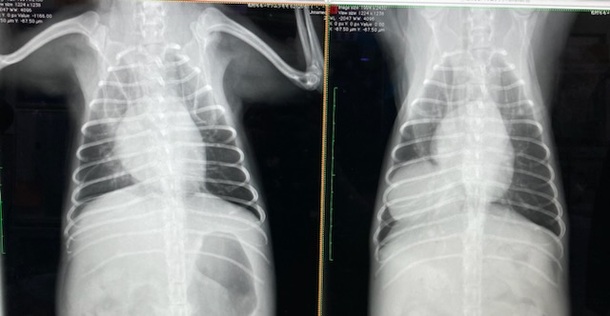

★レントゲン写真★

右→手術前

左→手術後

肝臓が元の位置戻りました😢